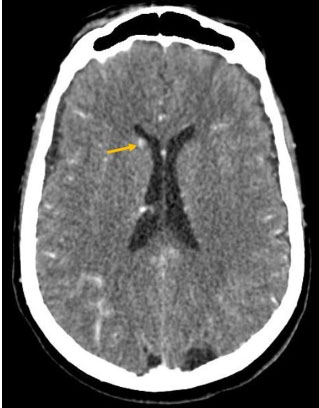

A brain CT was performed, showing multiple supra and infratentorial nodular lesions, homogeneously enhanced after contrast (Figure 1 and Figure 2).

Figure 1: An axial pre-contrast CT image showing a spontaneously hyperdense nodular lesion in the right caudate nucleus (arrow).

They often appear spontaneously hyperdense (75%), hypodense (22%), or isodense (3%), with post-contrast homogeneous nodular enhancement or ring-like pattern [8].